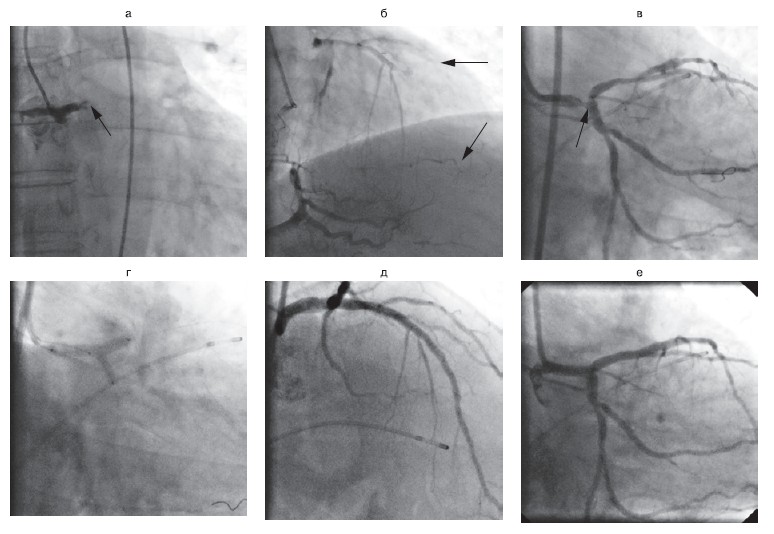

Рисунок 4.Пациент У., 42 ГОДА. Диагноз: Q-позитивный нижний инфаркт миокарда. Реканализация правой КА при помощи микрокатетера для аспирации тромбов "Diver". Применение микрокатетера для аспирации тромбов позволило избежать дистальной эмболизации коронарного русла.

а — окклюзия правой КА в дистальном отделе с образованием тромба; б — коронарный проводник, заведенный через место окклюзии, дистальное русло не визуализируется; в — остаточный стеноз после аспирации тромботических масс микрокатетером «Diver»; г — конечный результат после стентирования артерии; КА — коронарная артерия.